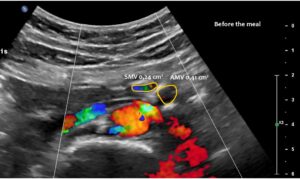

Normal size of the superior mesenteric vein which is slightly slimmer than the superior mesenteric artery as long as the patient was fasting. However, due to the limited space in the flat upper abdomen the superior mesenteric artery already is shifted to the left side of the aorta instead of lying precisely in front of it.

Here, the unique mechanism causing compression of the duodenum by the enlarged superior mesenteric vein is demonstrated. In contrast to conventional SMA syndrome, the superior mesenteric vein acts as a pillar against which the aorta presses, thus obstructing the duodenum. It is important to be aware of the variability in the position of the superior mesenteric artery in patients with a flat abdominal cavity. When the stomach is full, it may shift further to the left (or right) of the SMA than in the fasting position.